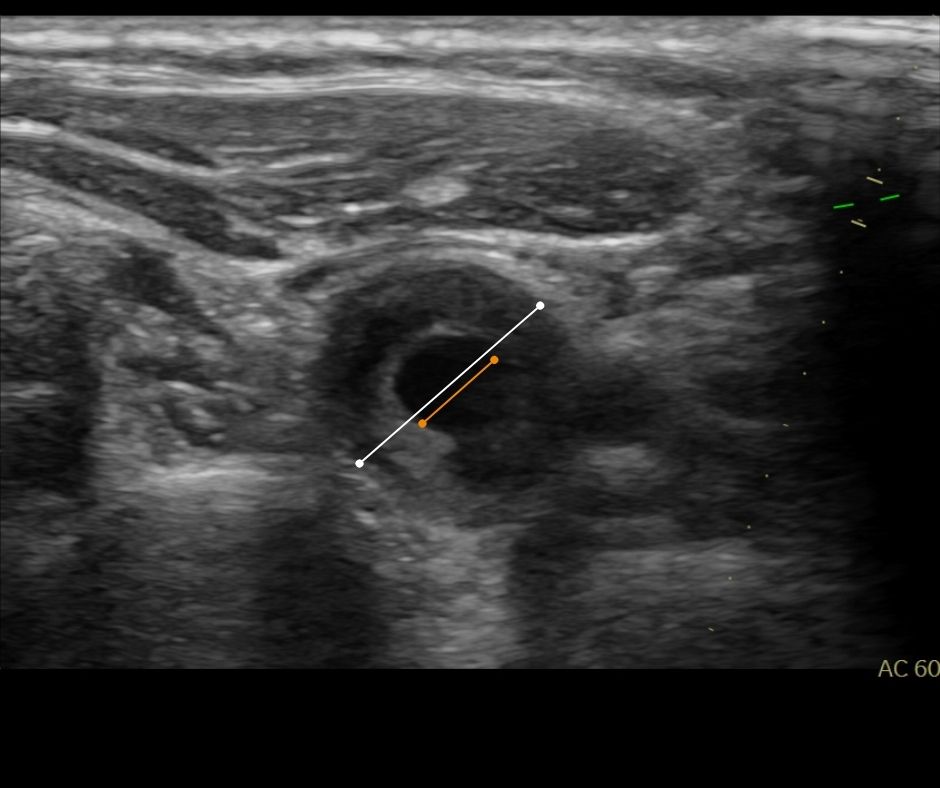

Ein Ultraschallbild mit markierten Linien über einem dunklen, runden Bereich in der Mitte.

Bildnachweis einer Verengung der Halsschlagader mit weichem Plaquematerial

Bei der auf die Anamnese folgenden Sonographie der Halsschlagadern dokumentierte die abgebildete Stenosemorphologie eine Verengung der Halsschlagadern, eine Karotisstenose.